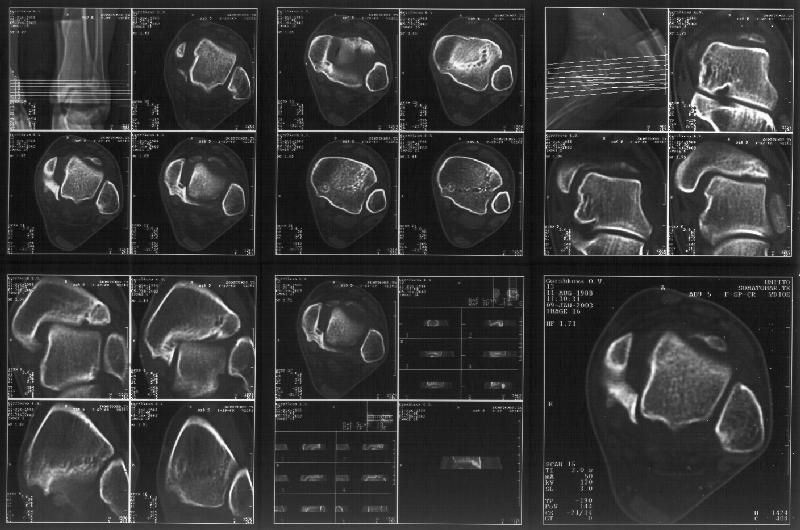

На следующий день пациентке сделали КТ. Может быть, после просмотра картинки будут другие предложения? Не убрать ли ве-таки этот фрагмент

позади внутренней лодыжки, который оттесняет таран кнаружи?

Думаю, КТ прочитан не верно. Задняя часть медиального маллеола, в сущности уже часть заднего маллеола стоит на месте и трогать её не следует. Передняя часть маллеола на 3-4 мм удалена от тарана. Сравните с пространством между

латеральным маллеолом и тараном. В норме все три должны быть одинаковы: между тараном и латеральным, задним и медиальным. Это главное условие устойчивого сидения тарана в голеностопном суставе.

Все-таки она как раз была была отколота и вместе с тараном смещена латерально.

> Передняя часть маллеола на 3-4 мм удалена от тарана.

Внутренняя лодыжка не была сломана, она как была на своем месте, так там и находится. Это таран от нее отдавлен кнаружи смщенным в его сторону фрагментом позади внутренней лодыжки. За счет чего и есть проявления нестабильности связок.

тибиальной основы. По мне, КТ это совершенно ясно показывает.

Мне в тоже время совершенно ясно видно по той же КТ, по 4 срезам, расположенным в центре и вверху пленки, что перелома внутренней лодыжки не было, в следующем собщении я приложу увеличенный фрагмент томограммы. А к этому письму прилагаю увеличеный фрагмент послеоперационной рентгенограммы, где выделил отколотый фрагмент

позади внутренней лодыжки. И он, как я вижу, находится между стержнем и тараном. А перелома внутренней лодыжки, и тем более смещения, IMHO

не определяется.

Здесь 4 среза, начиная от основания лодыжки и проксимальнее. Где, по Вашему мнению, проходит линия перелома, отделяющая переднюю часть внутренней лодыжки от большеберцовой кости? Заранее спасибо.

Я пометил линию перелома черной линией.

К сожалению на последних присланных срезах КТ нет более низкого, через таран, среза, который был на прежнем майле. На XR я попытался показать

На КТ я попытался изобразить скромными своими способностями (А)- место перелома, (С)- нормальный суставной зазор меж тараном и тремя его маллеолами. (В)- образовавшийся в результате перелома широкий раза в три зазор, позволяющий, по-моему, сублюксацию тарана при ходьбе. В свете данных КТ, критически важных, я бы предложил вертикальную остеотомию места перелома

задне-внутренним подходом и фиксацию мед. маллеола прижатым к тарану с помощью тонкого compression screw. После этого гипсовый сапожок и немедленное расхаживание ноги.